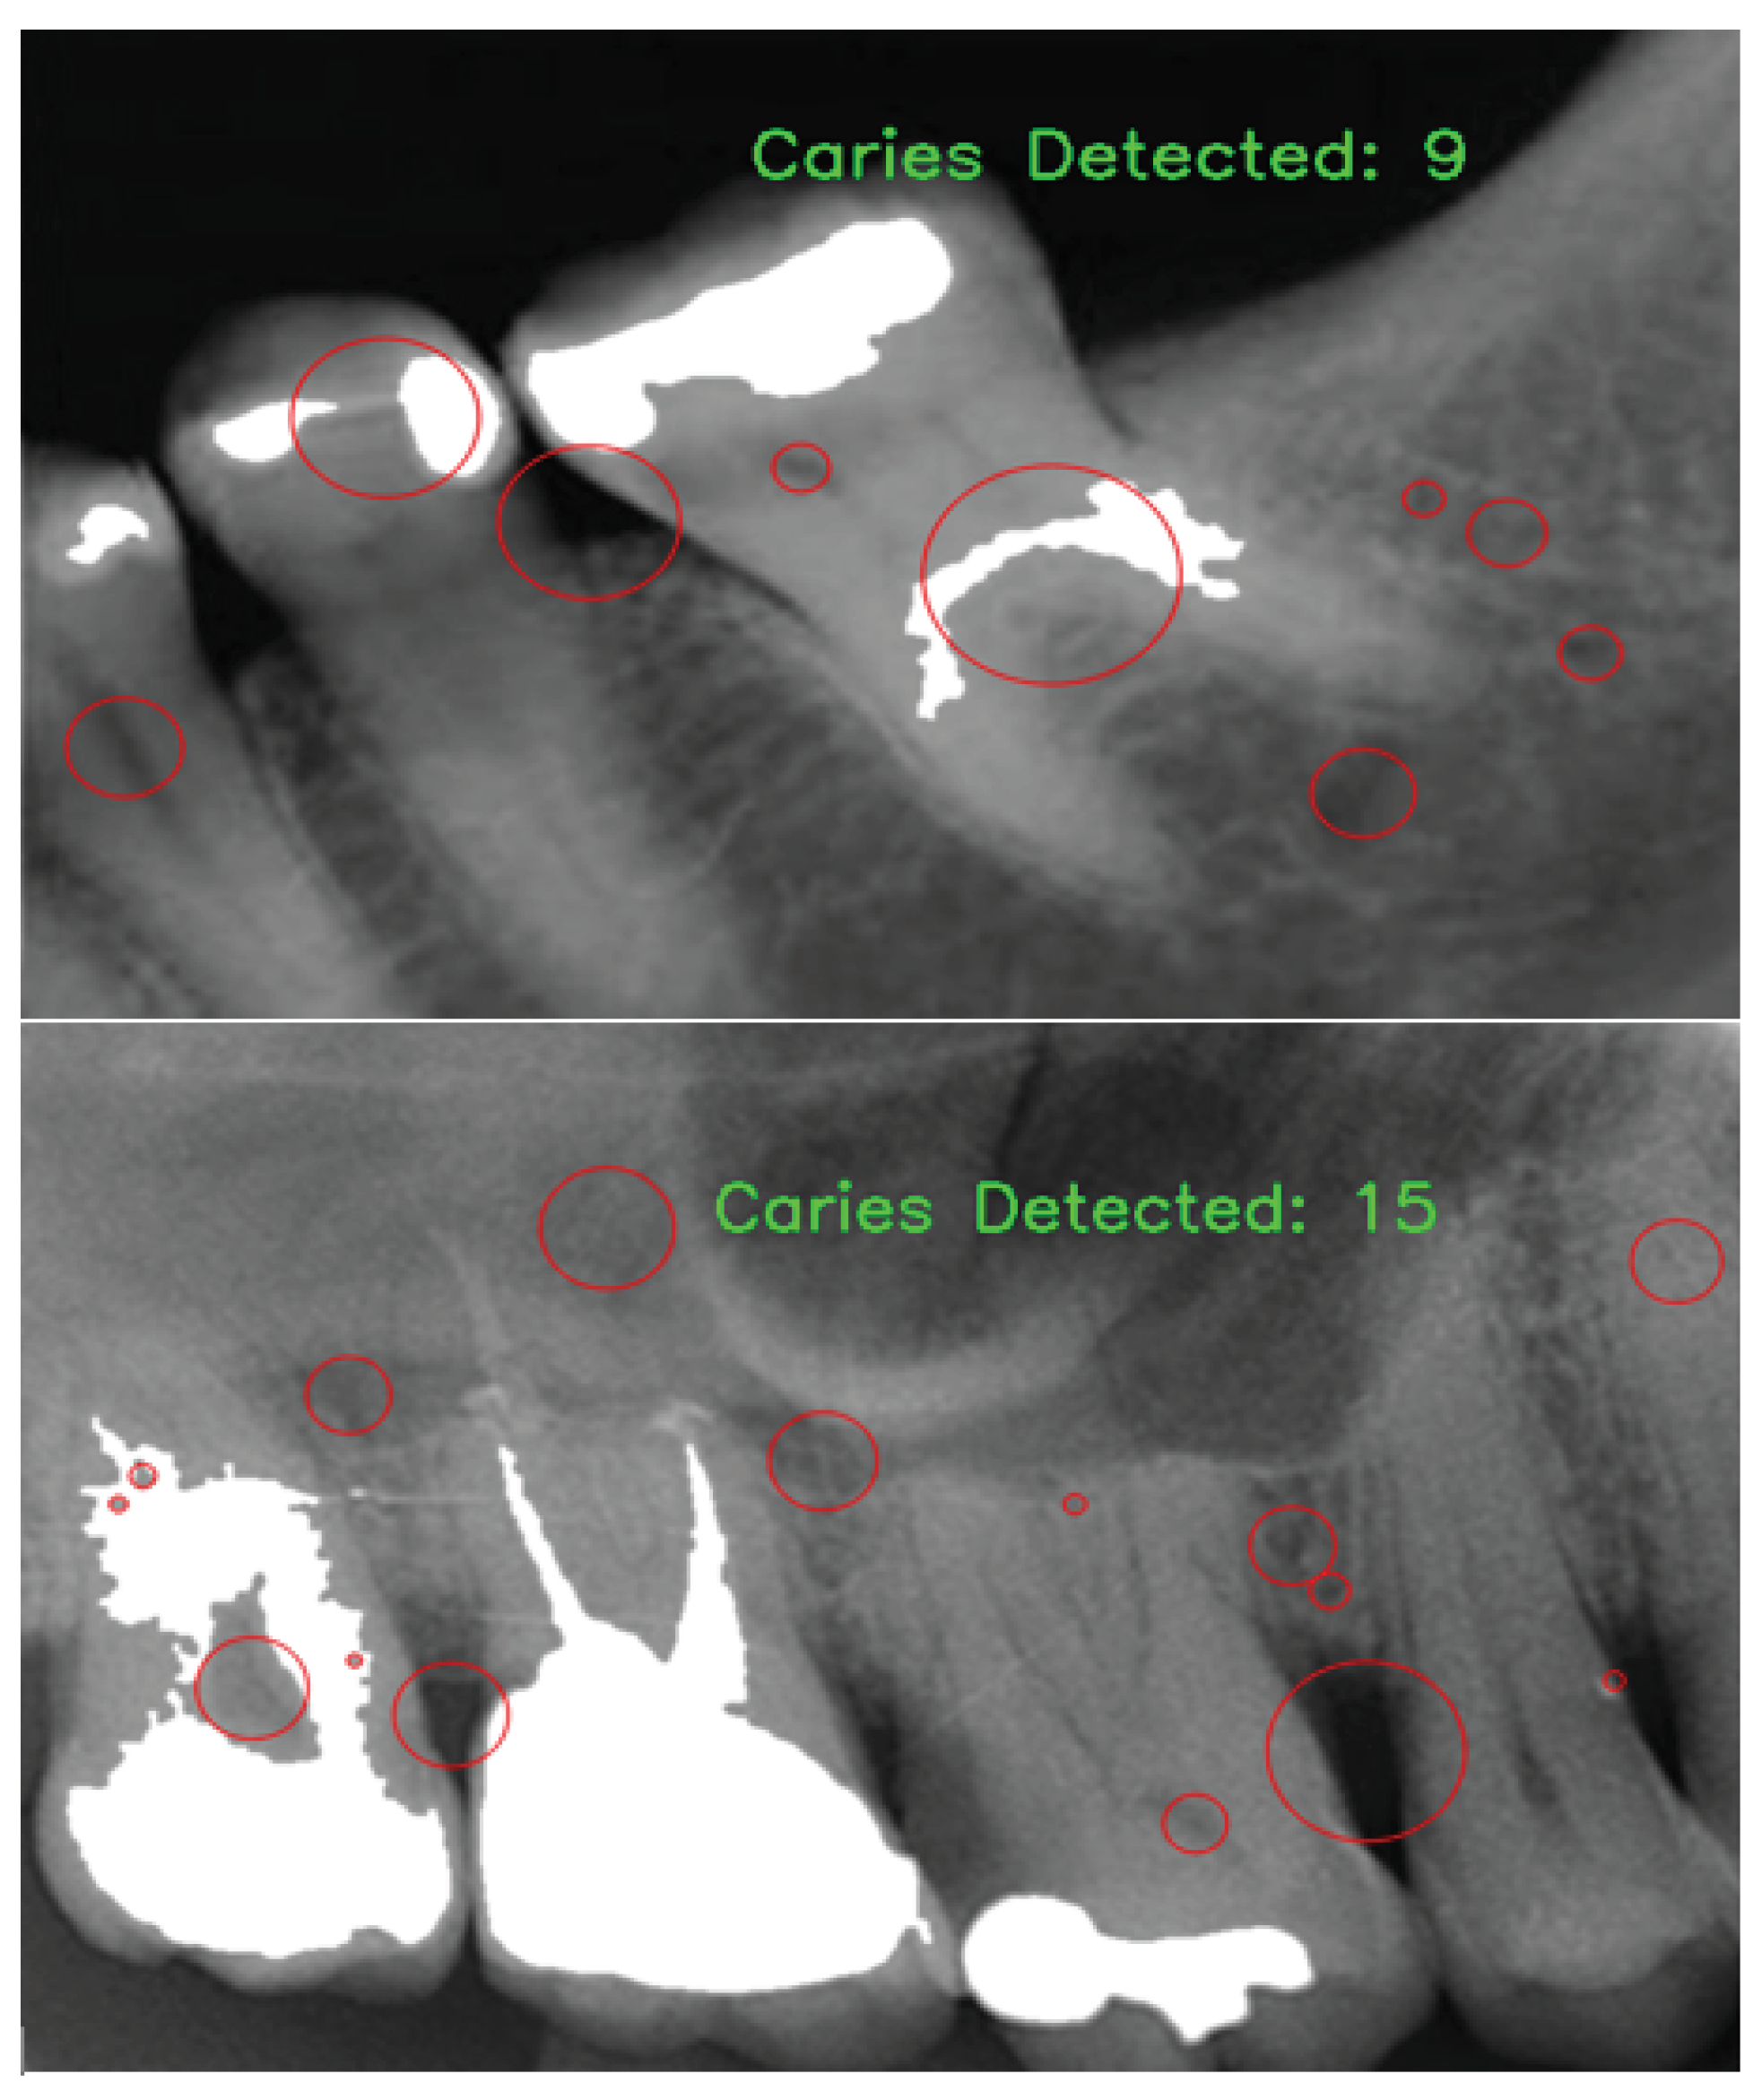

2.3.2. Caries Candidate Detection

2.3.3. Caries Candidate Selection

3. Results and Discussion